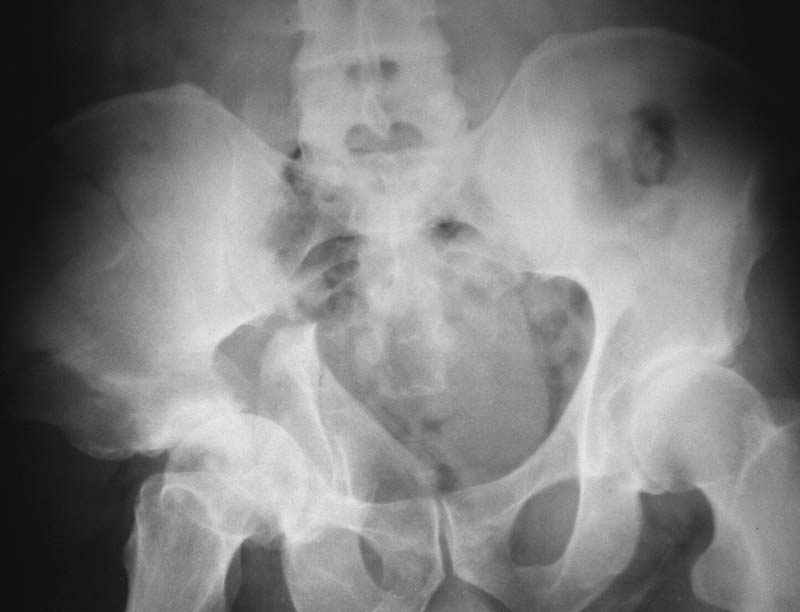

Посылаю схемы и 3D реконструкцию подобного повреждения. Называется он полным высоким двухколонным переломом вертлужной впадины, а "переломы крыла и тела подвздошной кости" входят в это понятие.

прикладываю схему доступа и случай.